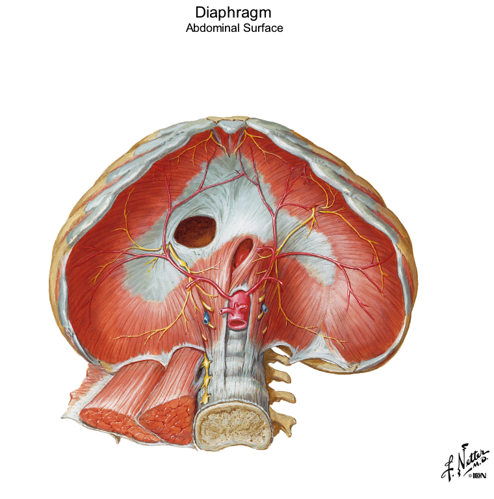

looking inside the diaphragm what can you see in the middle? what color is it? what does it serve as?

name the 3 openings of inside the diaphragm? point them out in picture

which hole opens through the central tendon?

central tendon

white

muscles all converge here on this central circle

central tendon is the upside down C

caval foramen is the big hole...opens up through the central tendon

esophageal hiatus is the oval oblong hole in center and inferior

aortic hiatus is the hole where you can even see part of the aorta coming through...most posterior of the 3 openings

what passes through these openings in the diaphragm?

Openings:

- Caval foramen...Inferior vena cava

- Esophageal hiatus...esophagus

- Aortic hiatus...Aorta

the sternal region of the diaphragm has attachments where?

the costal part has attachments where?

the lumbar part has attachments where?

Regions:

- Sternal part...attachments “along sternum”

- Costal part...attachments “along ribs”

- Lumbar part...attachments “along quadratus lumborum and psoas”

in picture: all regions form around the central tendon...small spot above is the sternal part...two huge kidney shapes on sides of central tendon are the costal regions...and the lumbar region is the space underneath the central tendon